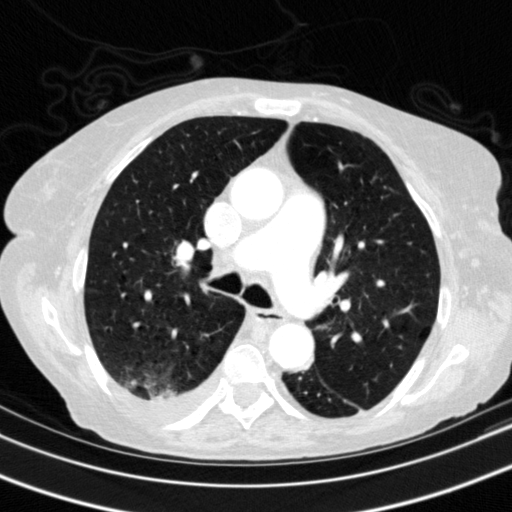

Generated VENOUS CT scan (A→B translation)

Mediastinum window (WL 40, WW 400 β†’ Low βˆ’160, High +240)

Actual HU range: [-160.0, 240.0]